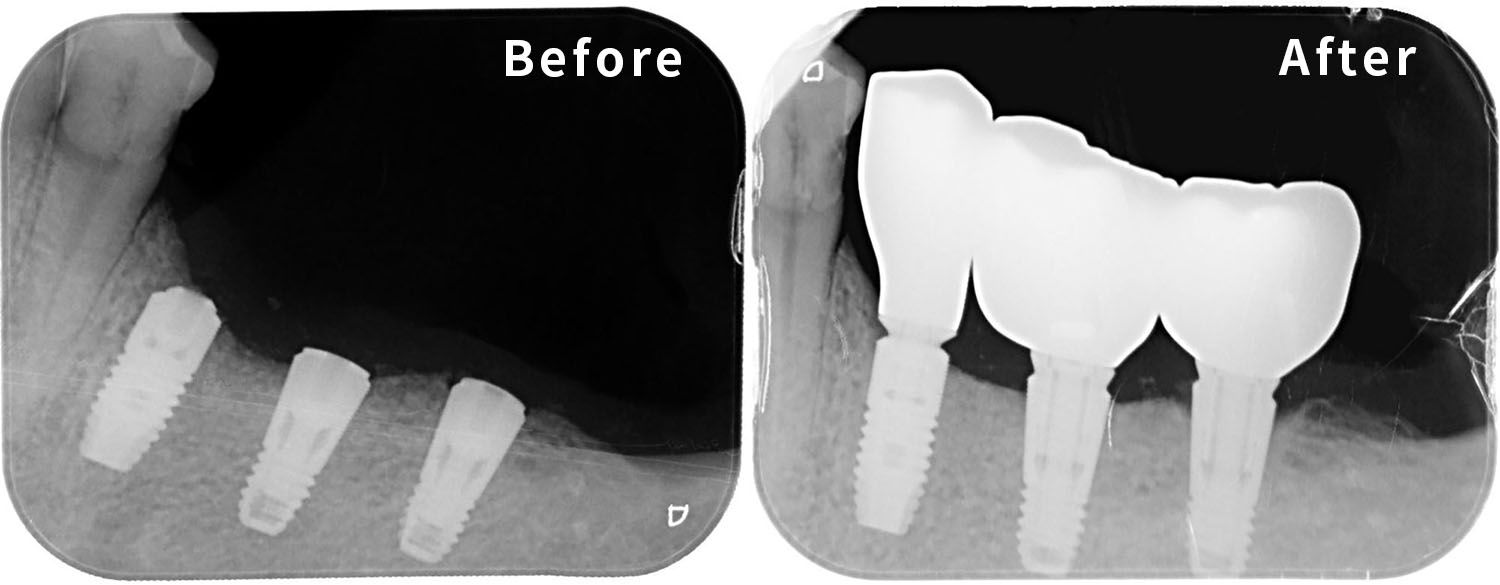

針對韓先生的狀況,我們的治療目標非常明確:必須恢復他左側的咀嚼功能,平衡雙側咬合。經過 3D 電腦斷層掃描(CBCT)的骨質評估後,我們制定了植牙治療計畫,鎖定的位置是左下顎的三顆關鍵牙齒:分別是「左下第二小臼齒」、「左下第一大臼齒」以及「左下第二大臼齒」。

在手術過程中,我們特別注重植體的位置與角度,因為下顎後牙區神經血管分佈較為複雜,我們精準地避開下齒槽神經,將三顆植體植入最佳的骨整合位置。

經過數個月的骨整合期,確認植體與骨頭緊密結合後,我們裝上了客製化的假牙,在設計假牙時,我們不只考量耐用度,更精細地調整了咬合面的型態,確保這三顆新牙齒能與對咬牙完美密合,這就像是幫汽車重新裝上了輪胎,而且是經過四輪定位的精準調校,目的就是為了讓韓先生在未來的二十年、三十年,都能放心大膽地使用這口牙。